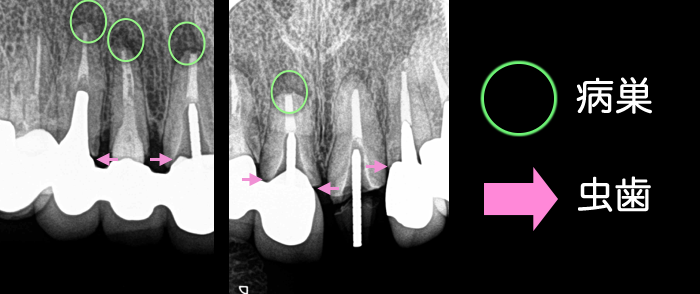

前歯の差し歯が取れて来院されました。差し歯が取れた歯は根の部分しか残っておらず、他の残っている歯の根の部分に虫歯が進行していました。レントゲンを撮らせていただくと、前歯の差し歯の中も虫歯が進んでおり根の先にばい菌が溜まって、いつ歯が取れてもおかしくない状態でした 。

状況をご説明したところ、患者さんは今後15年不自由なく食事と綺麗な歯を手に入れたいとご希望されたのでインプラントをご提案します。前歯は審美的において治療中に歯がないと患者さんが困りますので、埋入治療と同日に仮の歯まで入れる計画にいたしました。

治療前には歯肉を引き締める必要があるので、クリーニングをおこないます。歯肉の炎症を取って、インプラントを入れるポジションを定めてから埋入治療をおこないます。きちんと計画立てて治療をおこなえば、写真のように埋入して即日に仮歯を固定する事も出来ます。